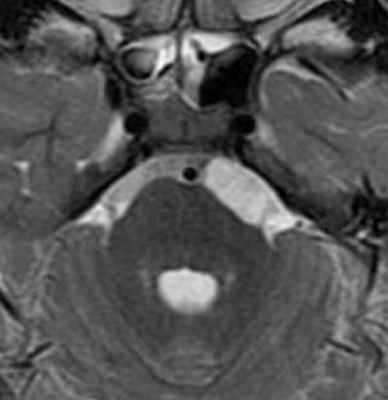

Киста смещает височный рог бокового желудочка и деформирует нормальный гиппокамп. Кисты хориоидальной щели имеют ликворную интенсивность сигнала на всех последовательностях. (а) МРТ, Т2-ВИ, корональный срез: определяется киста хориоидальной щели, смещающая височный рог бокового желудочка и вызывающая сдавливание и деформацию гиппокампа и парагиппокампальной извилины.

(б) МРТ, FAIR, аксиальный срез: у молодого взрослого с жалобами на головную боль определяется случайная находка - киста хориоидальной щели, расположаенная медиальнее височного рога бокового желудочка.

Такие доброкачественные кисты имеют ликворную интенсивность сигнала на всех последовательностях, включая ДВИ, и не накапливают контраст.

Эти кисты обычно не требуют лечения, кроме случаев связи с медикаментозно рефрактерной эпилепсией.в) Дифференциальная диагностика кисты хориоидальной щели: